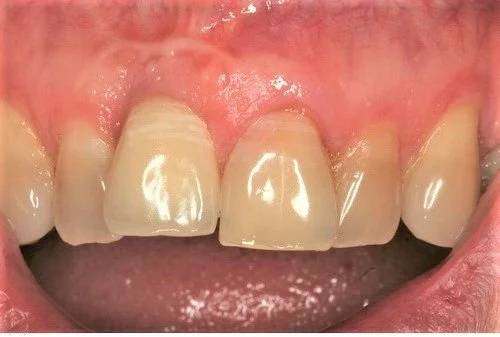

The photo below shows the post operative result one hour after extraction. Note the relative continued eruption (and alveolar bone growth) of the surrounding dentition compared to implant crown 11 placed 20 years ago. This is a common problem when implants are placed in young patients in the aesthetic zone.